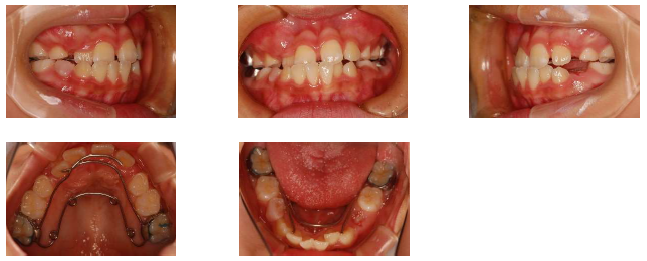

まずは裏側から顎を広げる装置をセットします。子供の歯が残っているこの状態では、顎もまだ成長できるため、その残っている成長を利用して顎を広げることで歯が生えるスペースを確保します。上の写真は治療から1か月後のものですが、右上の2番目の歯が少し表側へ移動しているのが分かるでしょうか。次回もこの症例の続きをお見せします。